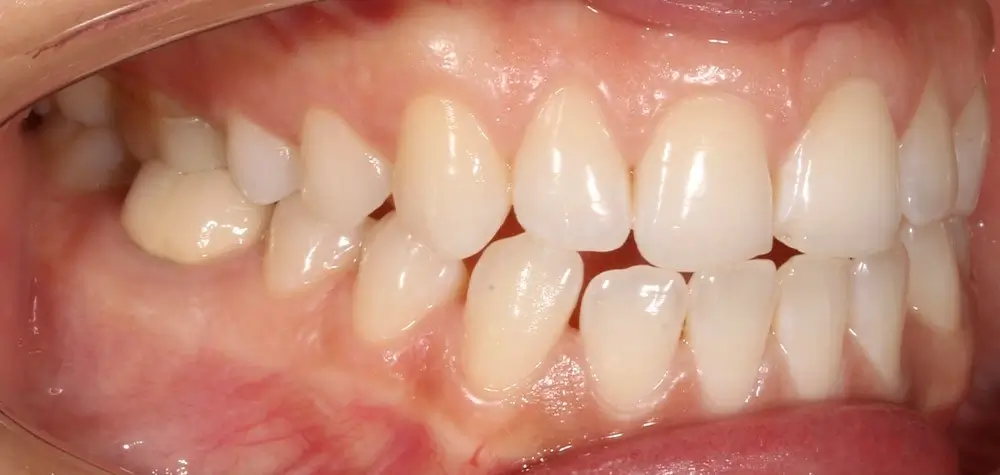

Открытый прикус - Кейс 5

Эффективность устранения дефекта прикуса посредством элайнеров FlexiLigner.

20

Количество кап НЧ

16

Количество кап ВЧ

Результаты лечения